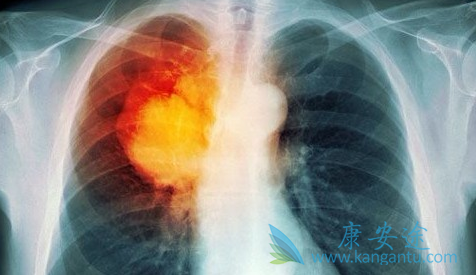

肺癌药物凯美纳/埃克替尼能取代化学治疗吗

今天看到一条消息,声称分子靶向药物凯美纳(盐酸埃克替尼)在晚期肺癌治疗中可以取代化疗。这是宣传作用还是真的呢?相信很多患者都蒙圈了。凯美纳的主要成分是盐酸埃克替尼,针对的是晚期不能手术的非小细胞肺癌,是国内自主研发的靶向药,确实给很多患者带来了希望。但凯美纳是否能代替化疗,还不能一概而论,患者的情况不同,有的情况复杂,是需要医生综合判断哪一种更适合。

那么哪种情况下,选择凯美纳(埃克替尼)是最好的?靶向药物,顾名思义,是找准肿瘤,像对准靶子一样攻击肿瘤细胞,而不伤害正常细胞。那么凯美纳就能找出EGFR突变类型的非小细胞肺癌肿瘤,对准攻击,对于不是这类型的肿瘤,效果可能不明显,所以一般在用这类靶向药之前,要做一个基因突变检测,看看是不是适合用。如果不做基因检测直接用,都属于盲试。